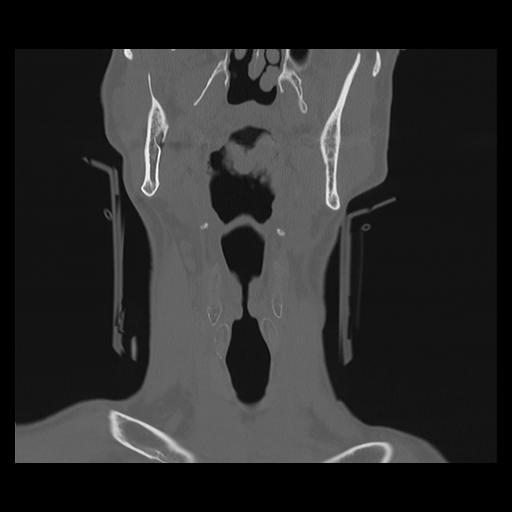

16 HUESO,,Coronal,2.000,HUESO,Coronal,